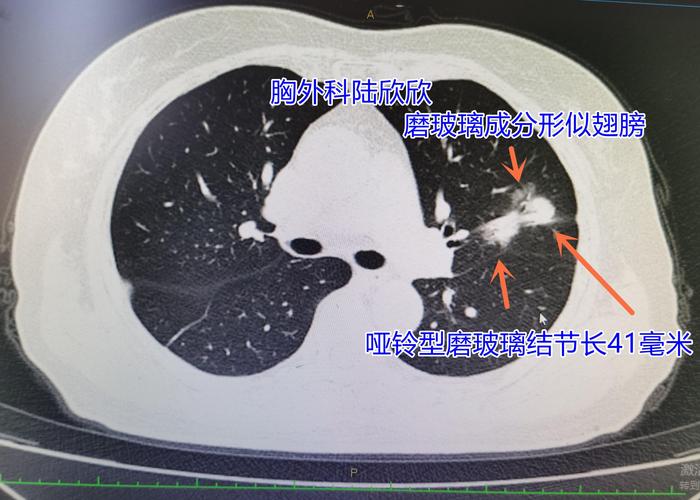

十五、长翅膀的哑铃形磨玻璃结节

可见2023年的哑铃形磨玻璃结节最大径41毫米,结节腹侧的磨玻璃成分看起来像是一个翅膀。病理是浸润性腺癌,亚型是腺泡亚型和贴壁生长亚型2020年时这个磨玻璃结节最大径21毫米,可惜当时的医生没有认出是恶性病变,误认为是炎性病变。